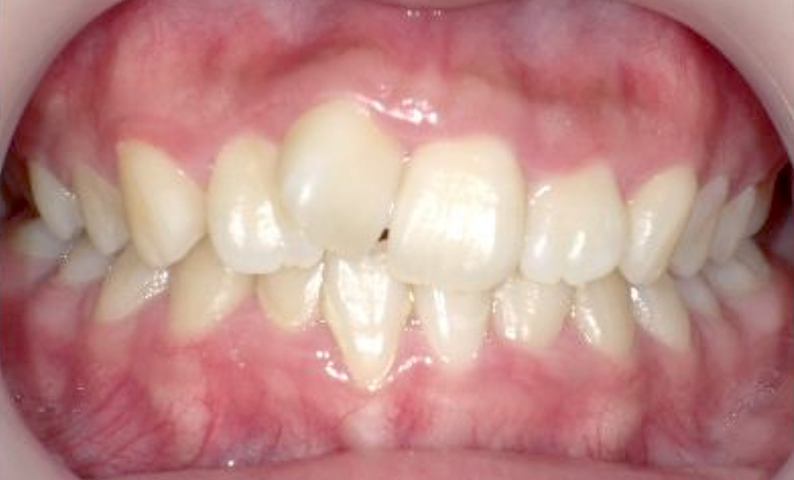

症例_004 上下顎の部分矯正

治療期間:8ヶ月金額:54万円+税女性前歯のガタガタ捻転歯

| Before | After |

|---|---|

|